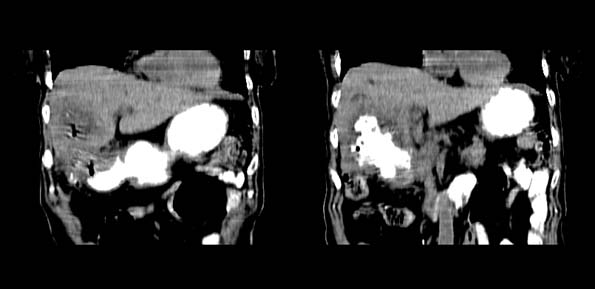

以下是引用bailaode在2008-6-12 22:10:00的发言:[br]资料中未提及患者有无急腹症体征,这个很重要。[br] ct表现:肝内境界模糊之低密度灶,内有含对比剂之液气平面.(提示肝内病灶与胃肠道沟通) [br] 1、根据“长城干红 ”所提供的资料“患者,女,74岁,黑便月余,消瘦,一般状况差,白细胞1万四千”,是否可认为是个慢性病程?那么我首先考虑:十二指肠结核,十二指肠--胆管瘘,继发胆道逆行感染肝脓肿形成。[br] 2、如有急腹症体征则考虑:十二指肠溃疡穿孔?十二指肠占位伴穿孔?

以下是引用拾荒者在2008-6-13 22:13:00的发言:[br]病灶与升结肠、肝脏及十二指肠关系密切,且结肠降段见造影剂影,支持结肠与十二指肠瘘形成,原因及原发病在哪不好定,不过,虽说有风险,但还是应该手术治疗,单纯抗感染估计不行。